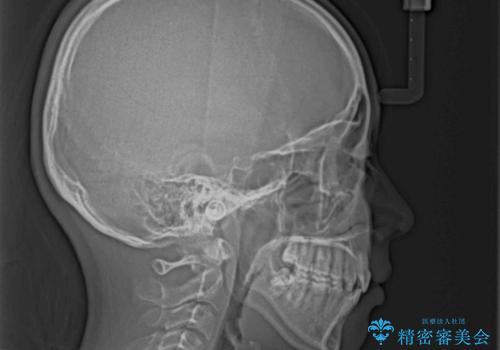

くちばしのように突出した前歯 口元を下げる抜歯矯正

- 上下の出っ歯を気にして来院された患者様です。

口元を積極的に引っ込めるために、上下左右の第一小臼歯を4本抜歯することとしました。

前歯部の突出と開咬は、舌突出癖によるものでしたので、舌のトレーニングをしっかりと行っていただき、1年半程度と短期間で治療を終えることができました。